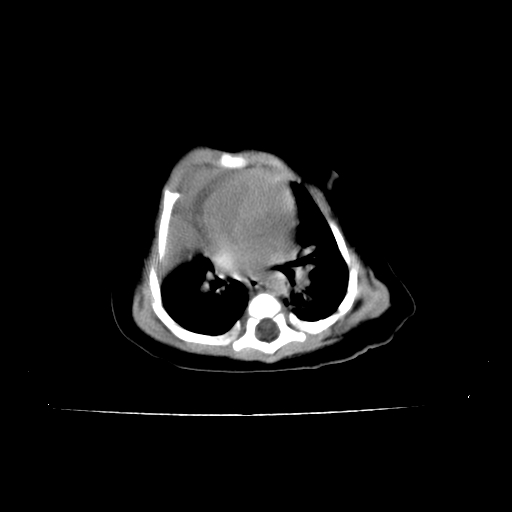

以下是引用影像之路在2009-5-8 15:46:00的发言:[br]1)胸廓畸形。2)考虑两肺感染性病变,并右肺上中叶肺不张;建议抗炎治疗后复查。3)胸腺肥大。4)前上中纵隔占位性病变待排;建议追踪复查。

以下是引用余辉在2009-5-8 8:44:00的发言:[br]鸡胸,胸腺肥大,双肺感染性病变,结合病史支原体肺炎可能性大